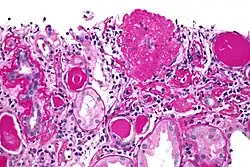

| Light micrograph of focal segmental glomerulosclerosis, hilar variant. Kidney biopsy. PAS stain. | |

On histology, FSGS manifests as scarring (sclerosis) to segments of glomeruli; moreover, only a portion of glomeruli are affected.[7][20][21] The focal and segmental nature of disease seen on histology help to distinguish FSGS from other types of glomerular sclerosis.[21]

Diagnosis of FSGS is made by renal biopsy that includes at least fifteen serial cuts with at least eight glomeruli.[32][33] Histologic features include sclerosis (scarring) of a portion (average: 15%) of the glomerular space, with only a portion of glomeruli manifesting any sclerosis.[33]